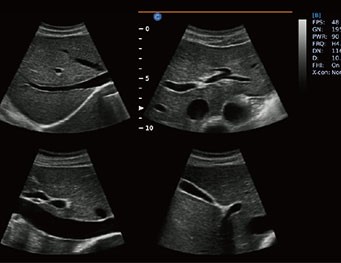

En la medicina humana, los ultrasonidos están diseñados para anatomías estándar, con variaciones según la edad del paciente. En veterinaria, en cambio, el equipo de ultrasonido debe adaptarse a una diversidad de especies y tamaños, desde perros y gatos hasta caballos y ganado. Esto exige configuraciones especiales de frecuencia y tipos de sonda para obtener imágenes precisas en cada tipo de paciente.

Las sondas de ultrasonido varían en frecuencia para obtener la resolución adecuada en cada exploración. En la medicina humana, se emplean frecuencias de entre 2 a 18 MHz, adaptadas a las distintas partes del cuerpo. En veterinaria, la variedad de pacientes requiere una adaptación mucho mayor: los animales grandes, como caballos, requieren frecuencias bajas para mayor penetración, mientras que los animales pequeños necesitan alta frecuencia para claridad en imágenes superficiales.

Los protocolos en medicina humana están bastante estandarizados, como los exámenes para el abdomen o el corazón. En veterinaria, sin embargo, los veterinarios deben ajustar sus protocolos a la anatomía y condiciones particulares de cada especie. Este conocimiento especializado en animales permite adaptar las técnicas de ultrasonido a cada situación clínica, brindando atención personalizada y precisa.